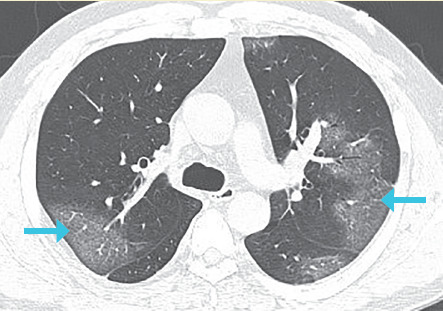

Estadio 1: De 0 a 4 días. El patrón en vidrio despulido fue el principal hallazgo radiológico, subpleural en los lóbulos inferiores, unilateralmente o bilateralmente (figura 2).